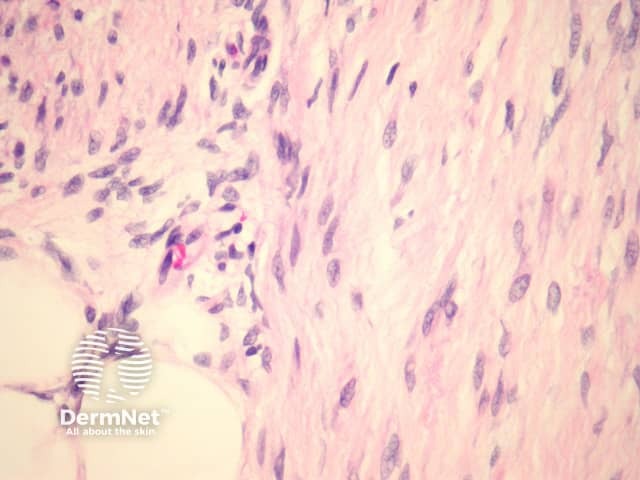

In fibrous hamartoma of infancy, bundles of well-defined thick connective tissue, which branch, interweave, and project into adjacent fat (figure 1). The lesion is composed of three components: adipose tissue, myofibroblasts (best seen in figure 2), and primitive mesenchymal cells (best seen in figure 3). The distinctive primitive mesenchymal tissue organized in distinct whorls, bands, or nests (figure 3). Myxoid change may be prominent.

Figure 2

The myofibroblasts stain with actin and calponin. S100 is negative.